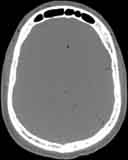

Visible Human male: Sectio transversalis 1058

CT